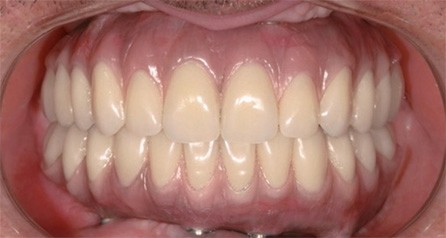

Całkowita przebudowa uzębienia

Pacjent z utraconym uzębieniem w wyniku próchnicy i choroby przyzębia np. paradontozy. W ich wyniku nie tylko utracił zęby i możliwość gryzienia pokarmów, ale przede wszystkim pewność siebie w życiu społecznym w kontaktach z innymi ludźmi, w dużej mierze wycofał się z wcześniejszego życia społecznego oraz, w swoim wyglądzie, postarzał się o kilka lat. Jednym słowem utracił w dużej mierze radość z życia.

Pacjentowi zaproponowano leczenie uzupełnieniem na stałe mocowanym na implantach. Całość zabiegową, tj. wstawienie implantów oraz zamocowaniem uzupełnienia wykonane jednego dnia. Tego typu rozwiązanie jest adresowane do osób zmagających się z bezzębiem (całkowitym czy częściowym), którzy chcieliby cieszyć się pełnią życia i którym stan ich uzębienia powoduje co najmniej dyskomfort.

Pacjent po zabiegu odzyskał pewność siebie w kontaktach międzyludzkich oraz w dużej mierze radość z życia, nie wspominając o pełnej i nieskrępowanej funkcjonalności nowych zębów.

Pacjent lat 73. Od wielu lat użytkujący ruchomą protezę górną. Pozostałe zęby własne z dużą ruchomością lub silnym zniszczeniem próchnicą w stopniu nie pozwalającym na ich leczenie.

Ze względu na stan swojego uzębienia pacjent czuł ogromny dyskomfort w kontaktach społecznych, miał też duży problem przy gryzieniu pokarmów – było to praktycznie niemożliwe i dlatego był skazany wyłącznie na pokarmy miękkie i płynne.

Pacjentowi zaproponowano kilka możliwości leczenia, z których wybrał uzupełnienie uzupełnienie mocowane na stałe na implantach. Zabieg wykonano wg procedury jednego dnia w wyniku czego pacjent wyszedł po zabiegach z nowymi zębami (cały łuk górny).